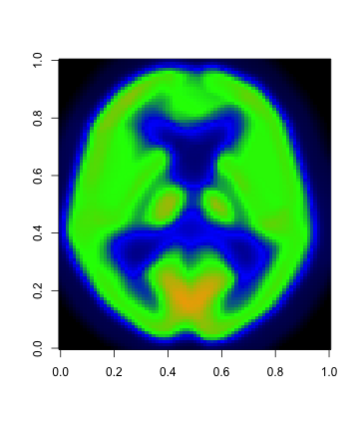

In this paper, we propose a robust estimator for the location function from multi-dimensional functional data. The proposed estimators are based on the deep neural networks with ReLU activation function. At the meanwhile, the estimators are less susceptible to outlying observations and model-misspecification. For any multi-dimensional functional data, we provide the uniform convergence rates for the proposed robust deep neural networks estimators. Simulation studies illustrate the competitive performance of the robust deep neural network estimators on regular data and their superior performance on data that contain anomalies. The proposed method is also applied to analyze 2D and 3D images of patients with Alzheimer's disease obtained from the Alzheimer Disease Neuroimaging Initiative database.